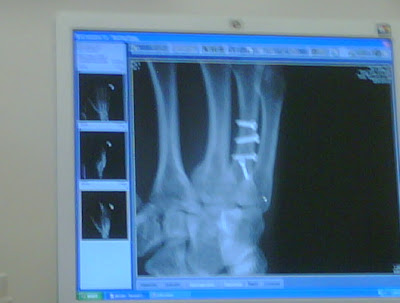

Here's a somewhat blurry X-ray of my hand. You can see the four screws going down my bone: the latest additions to my body.